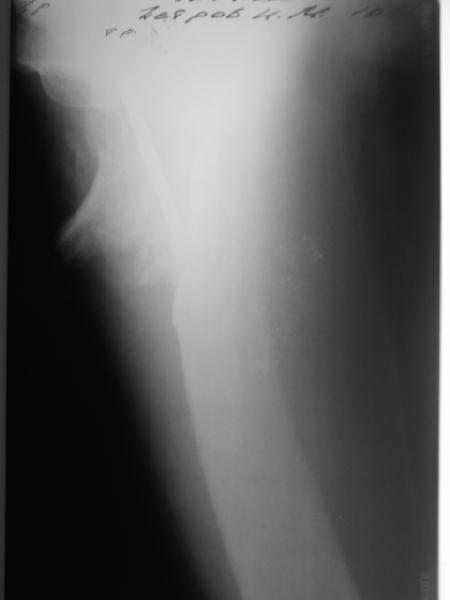

В приложении пример пациента, близкого по картине к тому, что

представил Виктор (варус и смещение периферического отломка на

поперечник кзади). Сделали как раз то, что Виктор исходно намеревался

- аппаратная коррекция и затем гамма.